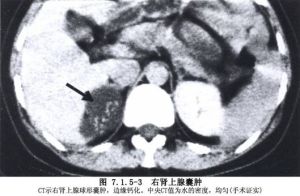

腎上腺囊腫多無症狀,常因體檢或其他原因檢查時發現,文獻中將之歸於腎上腺偶發瘤中,腎上腺囊腫較大時,可因壓迫周圍臟器出現腰腹部脹痛及胃腸道不適等非特異性症狀,少數患者可因囊腫破裂出血引起急腹症,手術探查時才被發現。可分為以下四型:1.內皮性囊腫

占45%,又分為淋巴瘤型和血管瘤型,囊壁內襯以光滑和平坦的內皮細胞為其特點。

2.假性囊腫

占39%,主要因腎上腺組織或腫瘤內出血所致,也可因腫瘤的囊性退行性

腎上腺囊腫3.上皮性囊腫

占9%,包括胚胎性囊腫,腎上腺囊腺瘤,真性或瀦留性囊腫3類,內壁襯以腺上皮細胞。

4.寄生蟲性囊腫

7%,以包蟲性囊腫為最多見,表現為壁厚,多鈣化,並可見頭節。